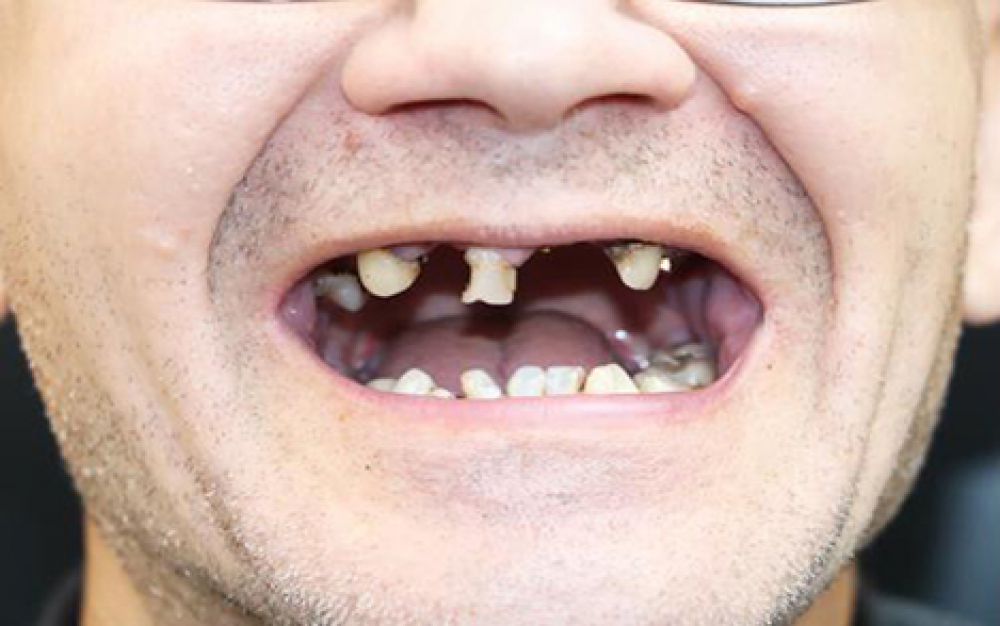

After

Dentures are removable appliances which are used as a replacement of missing teeth and tissues. They are the artificial teeth which enable normal functioning of human mouth. Dentures are of two types – Complete & Partial. Complete dentures are advised when all the teeth are missing, and partial dentures are applied when some natural teeth are missing. They are custom made especially for a set of teeth and gum line. Complete Dentures fit over the upper teeth and roof and on the lower teeth placed like a horseshoe. They are conventional dentures and are removed during the night for cleaning. Partial Dentures consists of replaced missing teeth attached to artificial gum connected by a metal framework which helps to hold the denture in place. Missing teeth can change the position of other teeth hence partial denture help to overcome this problem and keep the teeth intact.